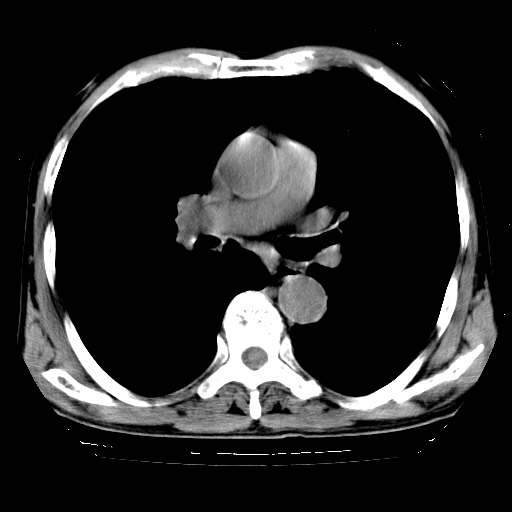

以下是引用hhcckk在2009-1-1 15:38:00的发言:[br]左下肺少许絮状模糊影--考虑感染[br]两肺散在小点状密度增高影--结合病史考虑矽肺?[br]气管壁钙化--可能由于老年退变性引起的